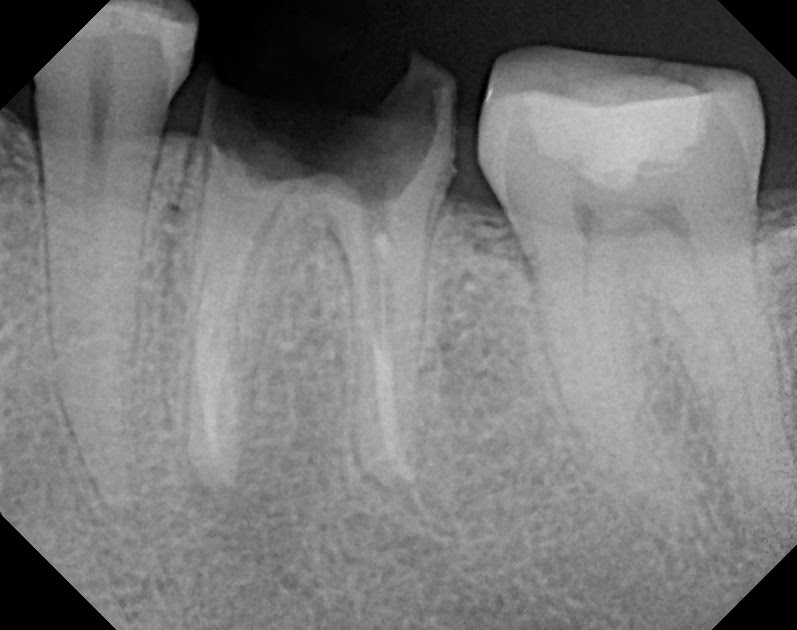

Failing Root canal xray YouTube Failed Root Canal Under Crown an illustrated guide to coronal leakage. This is not due to a failed root canal per se | how it causes root canal failure. In these scenarios, or if the tooth suffers a trauma, bacteria can be reintroduced into the root canal. If decay has gotten deep down into the tooth nerve, the recommended treatment is usually a root. Failed Root Canal Under Crown.